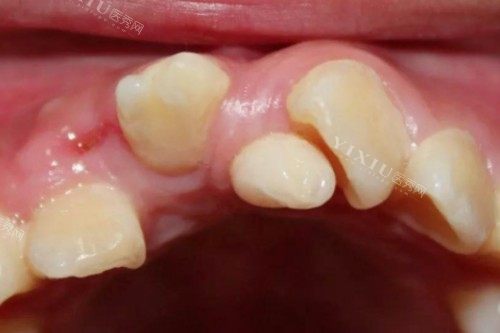

看设备:正规机构应配备CBCT、智能化口扫仪、种植机等基础设备,警惕仅用普通X光片的机构。

查病例:要求查看医生同类病例术前术后CT对比,重点观察骨结合情况及牙龈形态。